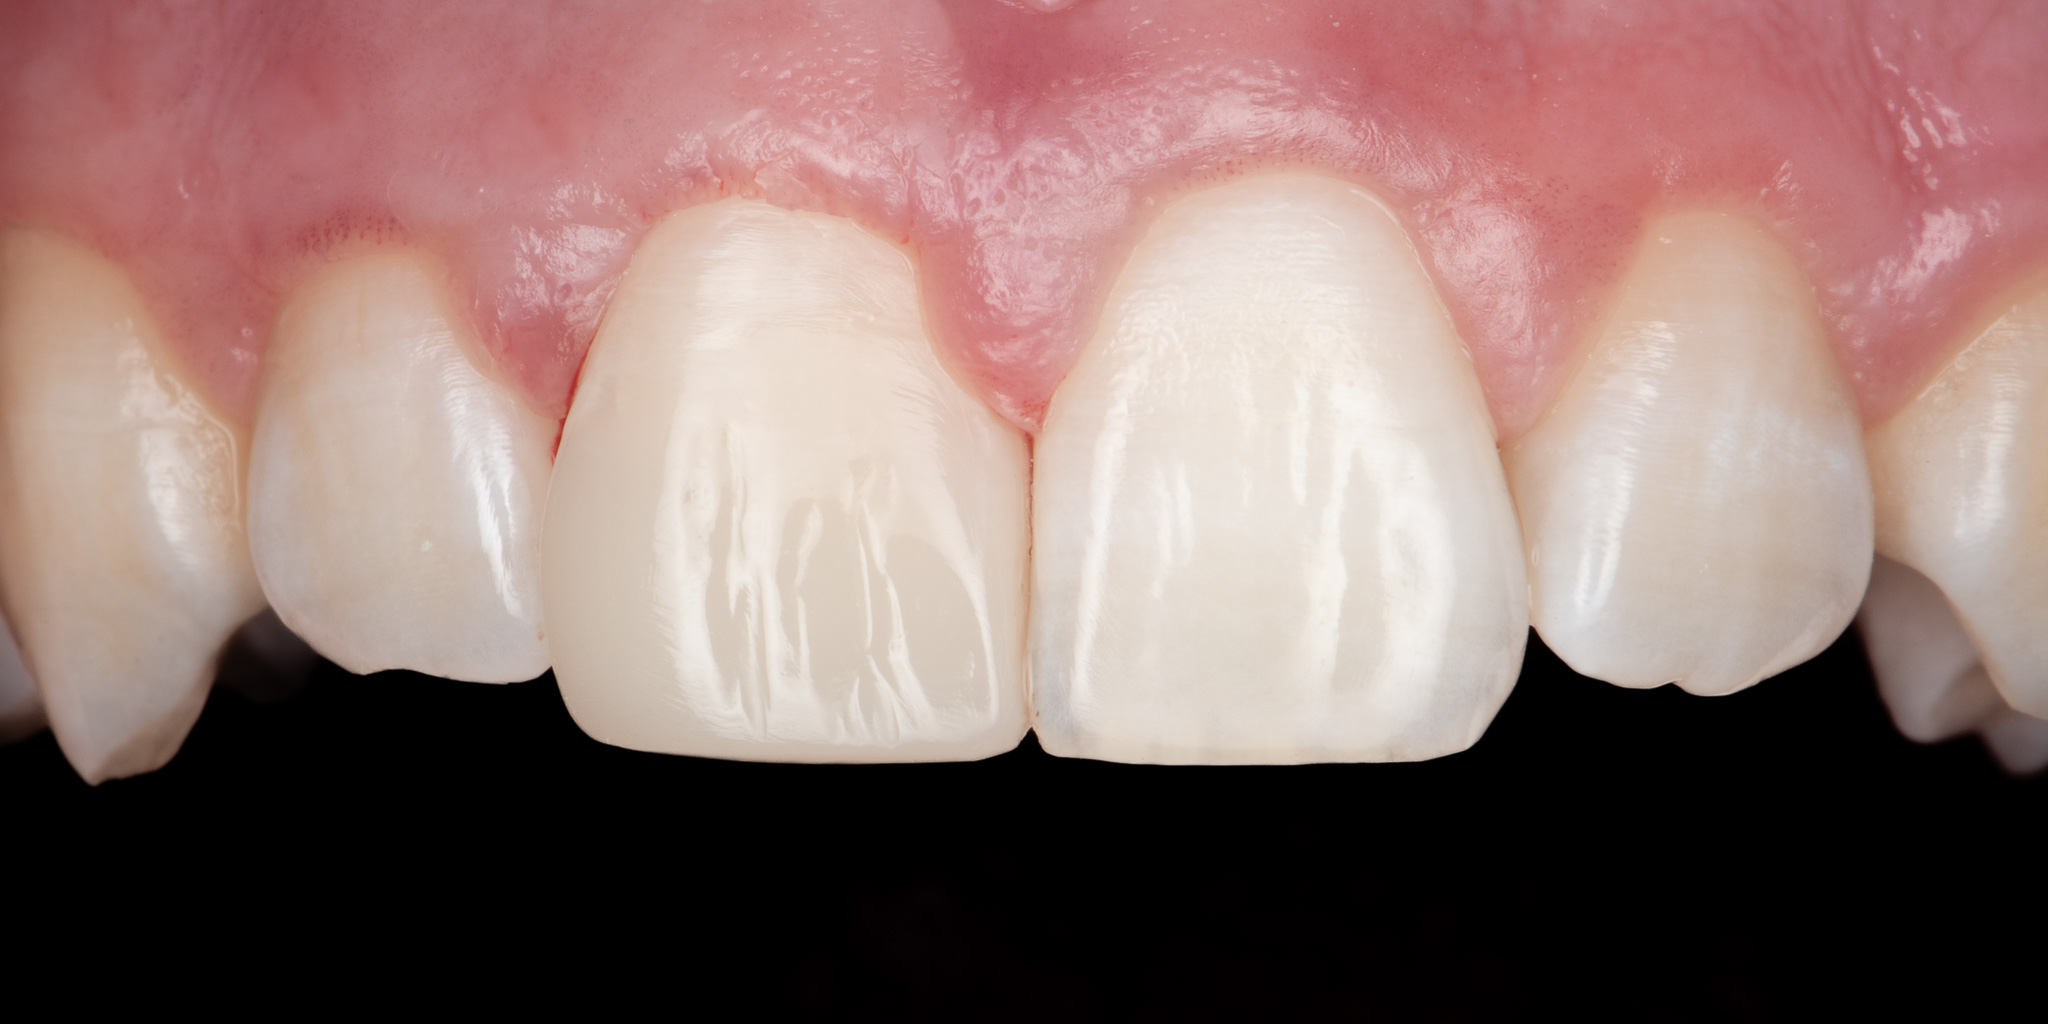

Pacjent 1

Pacjent zgłosił się podając złamie prawego siekacza centralnego (jedynki) w wyniku urazu. Wykonano estetyczną odbudowę biomimetyczną materiałem kompozytowym 3M™ Filtek™ Universal zapewniającym wysoką estetykę a także podniesioną odporność mechaniczną w porównaniu do konwencjonalnych wypełnień.